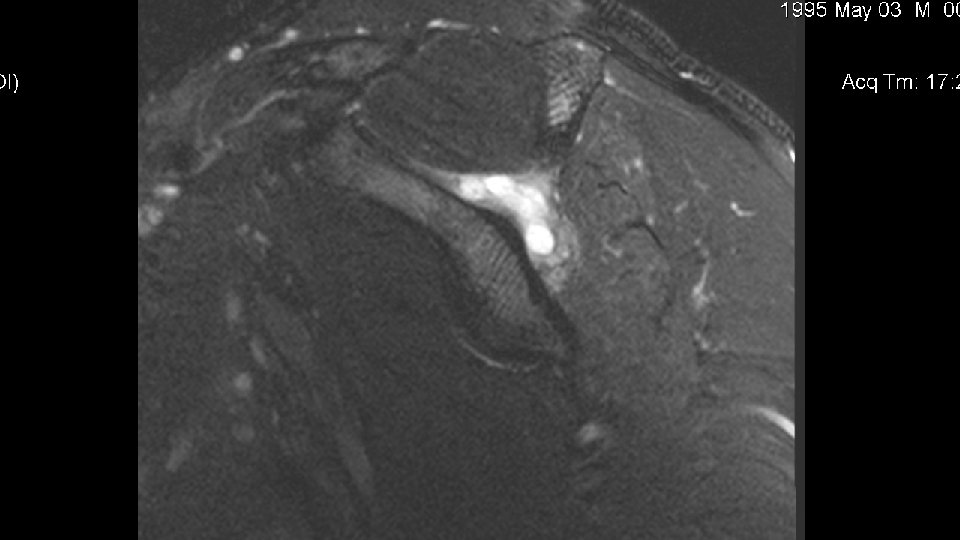

Disposition • The patient was scheduled for MRI